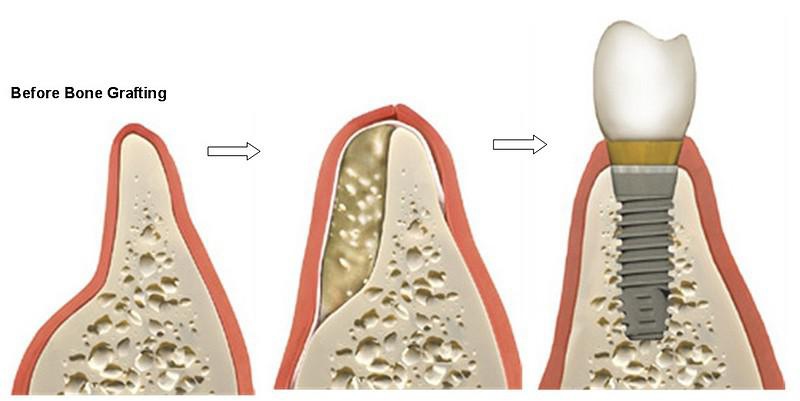

我的醫生說我需要補骨頭,那是什麼呢?

植牙從以前主要以外科手術考量的術式(意即植在易於植入的地方)

到現在主要是以補綴物考量(即以製作穩定的假牙為最終目的)

若是在評估最佳的植入位置,卻沒有最好的骨寬,骨厚度的話,就

需要補骨頭。補骨包含上顎竇提升術式,骨塊移植,或是骨粉。

若是需要補骨的植牙,就需要更長的等待時間,過程也較為繁複。

但為了最終理想假牙的製作,是很值得的。